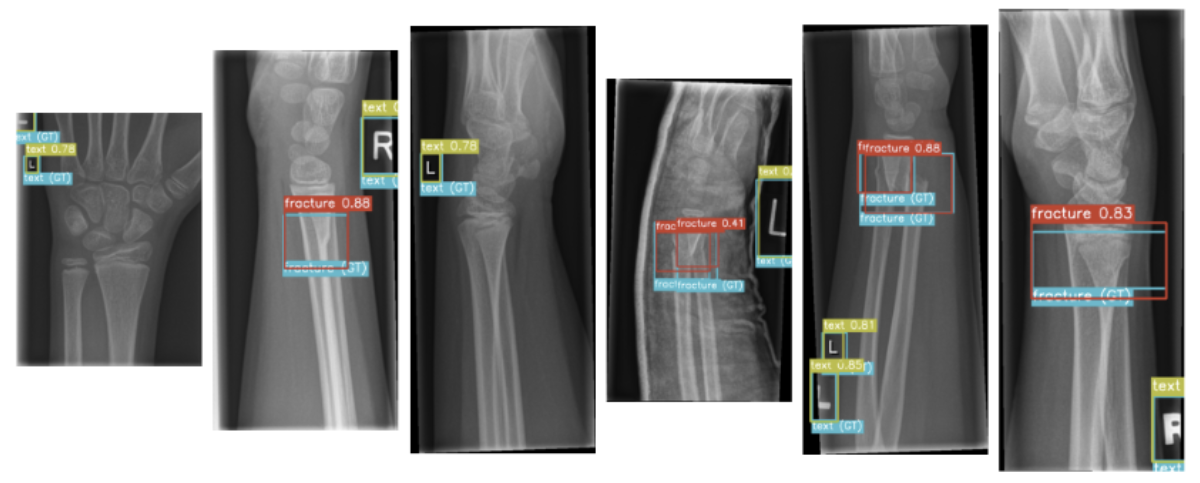

通用数据集(如 COCO)往往掩盖了真实业务场景的残酷性。以最新开源的 GRaZPEDWRI-DX 小儿腕骨 X 光数据集(包含超两万张高分辨率影像、极端的类别不平衡、模糊的边界)为例,传统的检测算法极易出现漏检和梯度消失。

fracture,metal,periostealreaction等)。在预处理流中,需解析原始的 JSON/XML 标注,计算出病灶中心的相对坐标 (xc,yc)(xc,yc) 与归一化宽高 (w,h)(w,h),将其无缝转换为 YOLOv7 所需的纯文本(TXT)格式,构建端到端的 DataLoader。

骨折检测(Fracture Detection)在 CV 中的本质是“极微小且边缘模糊的细粒度目标检测”。随着 CNN 层数加深,这种高频细节极易在下采样中被抹除。YOLOv7 通过重构主干网络(Backbone)解决了这一痛点:

医学影像标注存在一个致命的 CS 痛点:标签的不可靠性(Noisy Labels)。据该数据集测算,即使是资深放射科医生,对同一骨折框的 IoU 一致性也仅有 0.70。传统的硬标签分配(Hard Label Assignment)会直接导致网络震荡。YOLOv7 的深度监督标签分配算法完美化解了此危机: